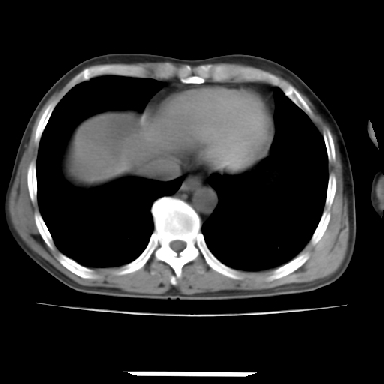

标题: CT7372:脂肪肝?外伤? [打印本页]

标题: CT7372:脂肪肝?外伤?

m 45 车祸,硬膜下血肿

肋骨无骨折,腹腔未见游离液体,所以不均匀脂肪肝首先考虑,但如果病人情况允许还是做个增强检查放心

考虑不均匀性脂肪肝,肝包膜下光整,肋骨无异常,无腹水征,不支持肝挫伤。